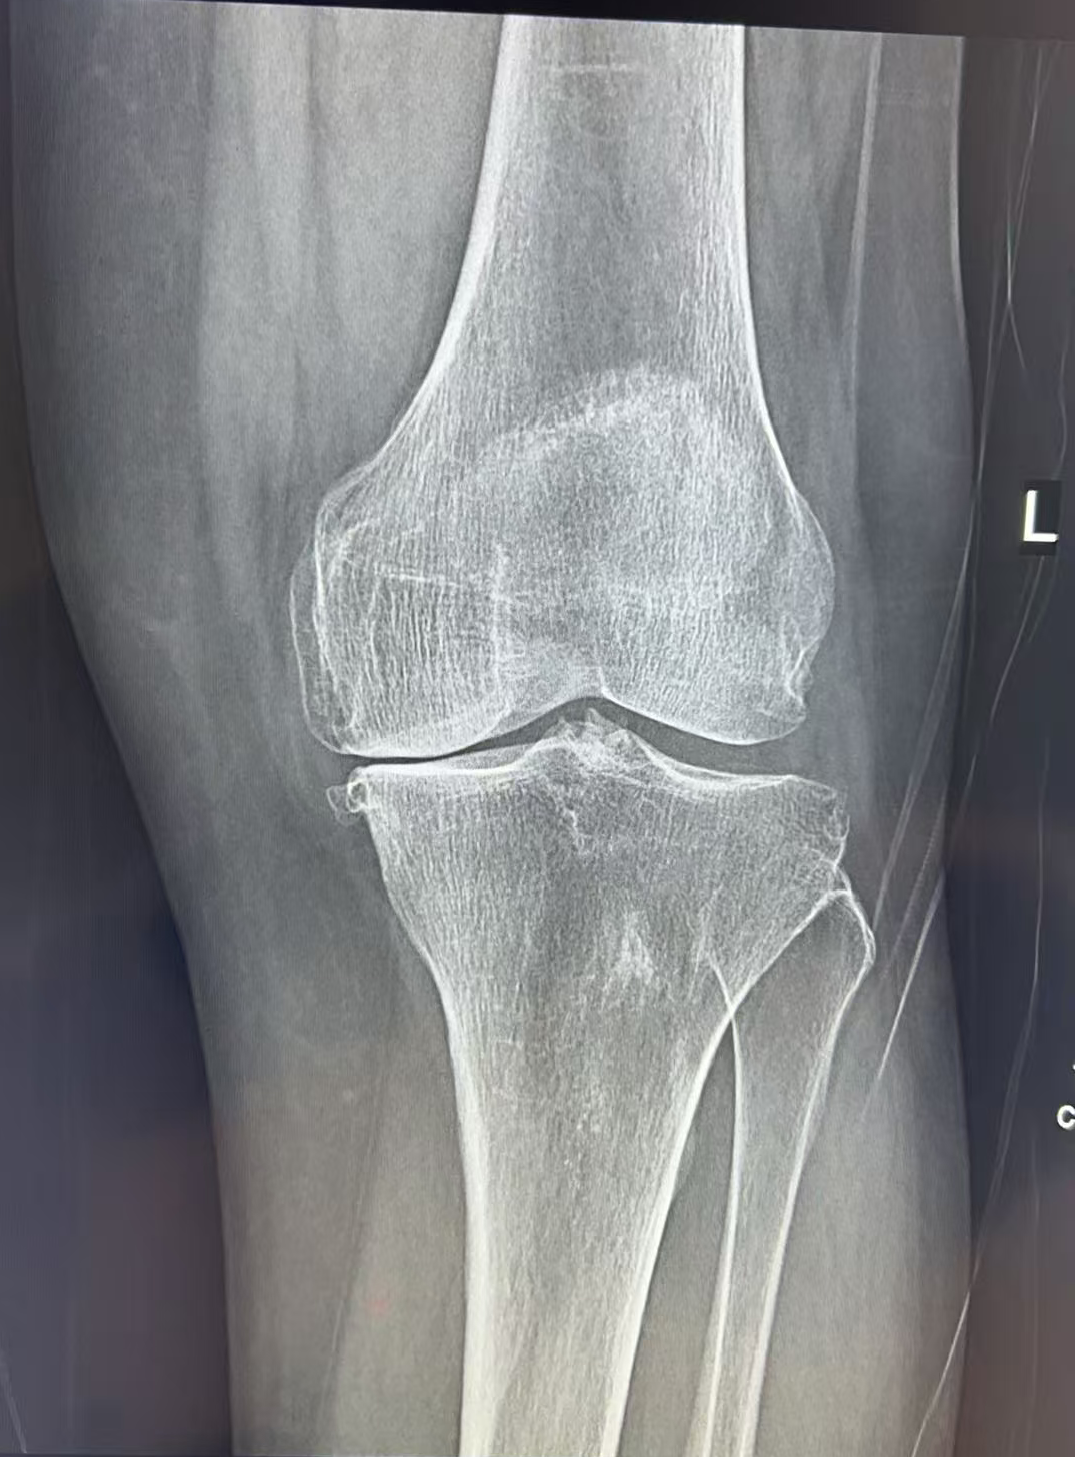

接诊她的是王歆峰主任,王主任耐心地听王阿婆讲了自己的情况,又仔细给她做了查体,还安排了详细的检查。最后确诊,王阿婆得的是 「左膝关节骨性关节炎」。

经过仔细评估,王歆峰主任决定给王阿婆做「左膝内侧单髁表面置换术」!这就是保膝治疗的一种,简单说,就是只修复膝盖磨损的那一部分,不用把整个膝盖关节换掉。手术很顺利。